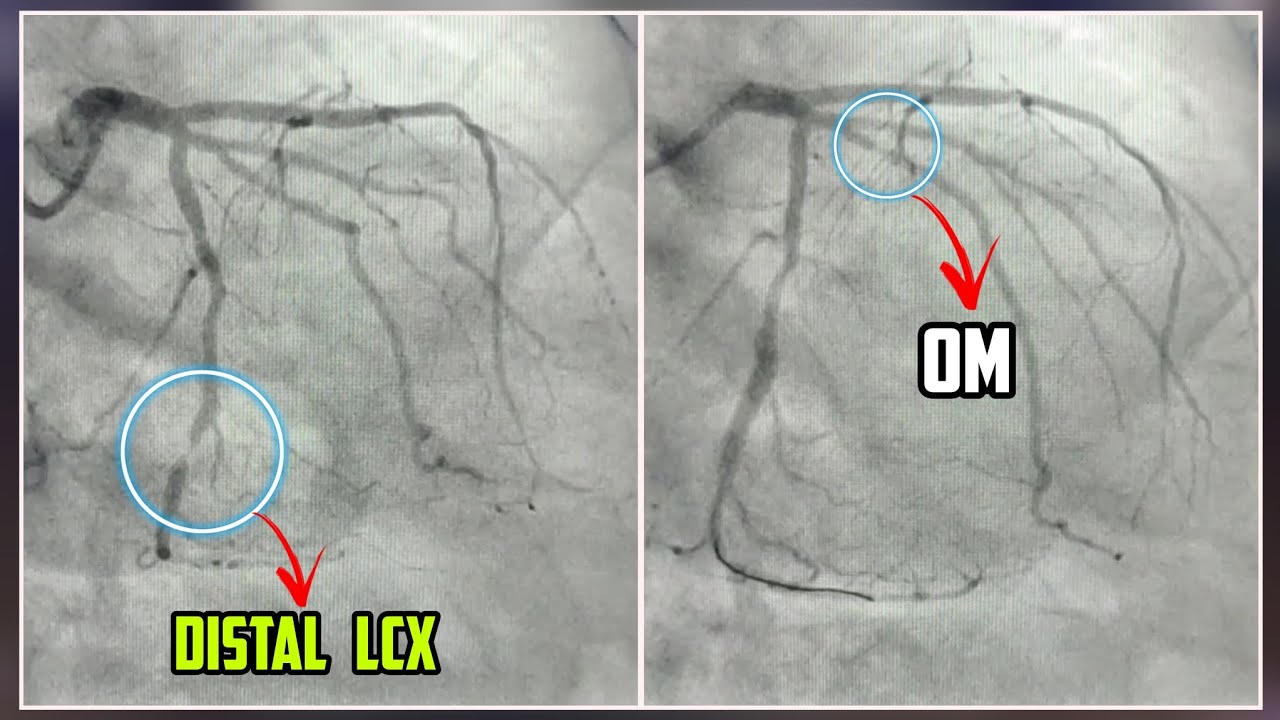

Angioplasty Treatment Double Vessel Stenting ( Distal LCX and OM 😮 Cath Lab Angioplasty The procedure also may be used as emergency treatment for a. Angioplasty and stenting for peripheral artery disease (pad) affecting the legs or. Treatments done in the cath lab include: Balloon angioplasty, with or without stenting. Angioplasty and stent placement may be a planned procedure to improve blood flow to the heart muscles. This type of angiogram doesn't need tubes. Cath Lab Angioplasty.